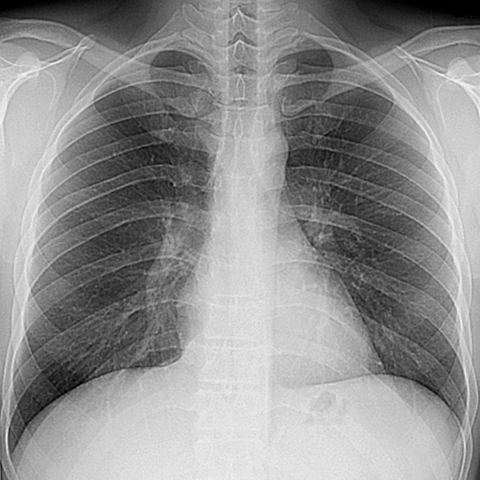

Normal PA Chest Radiograph on Inspiration [1 of 2]